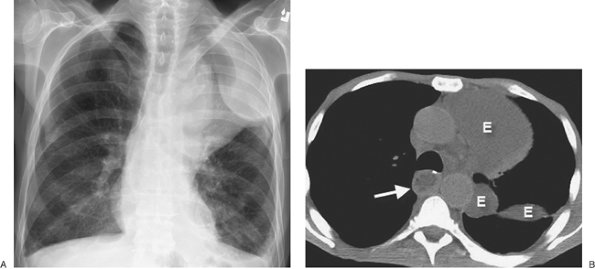

FIGURE 9-6. Pleural and pericardial effusions. A: PA chest radiograph of a woman with hypothyroidism shows blunting of the right costophrenic angle, producing a "meniscus" (arrow). B: Lateral chest radiograph shows blunting of both costophrenic angles posteriorly (arrow). C: CT shows bilateral pleural and pericardial effusions (E).